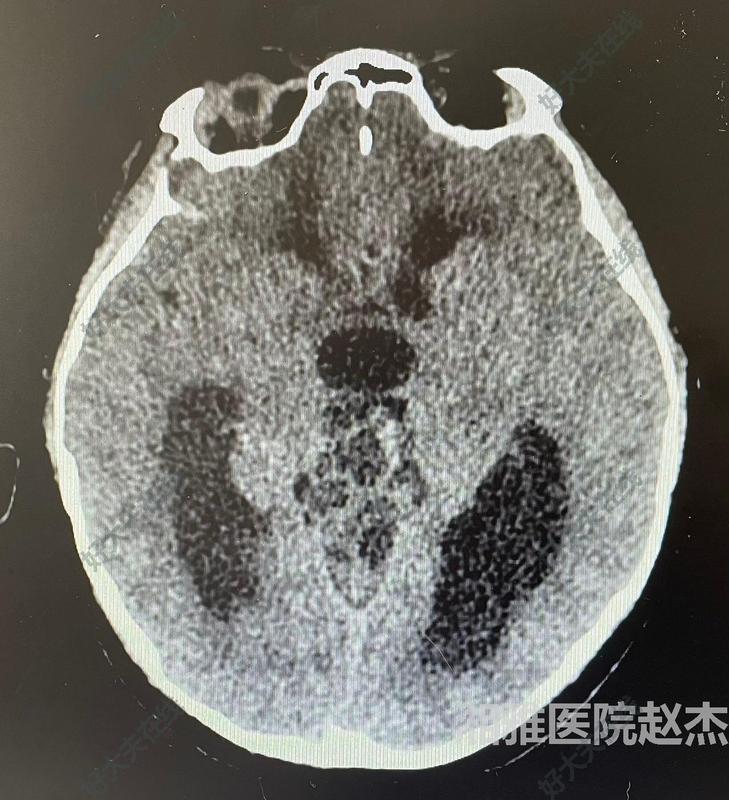

三腦室腫瘤

治療前男,12歲,頭痛4年,加重伴行走不穩(wěn)3月入院。外院頭部磁共振檢查顯示三腦室后部松果體區(qū)占位考慮畸胎瘤可能。入院診斷考慮:松果體區(qū)占位生殖細胞腫瘤。治療中在全麻下行經(jīng)幕下小腦上入路全切除腫瘤。術(shù)中病理為畸胎瘤。治療后治療后7天術(shù)后恢復好。

趙杰醫(yī)生的科普號2024年04月24日102